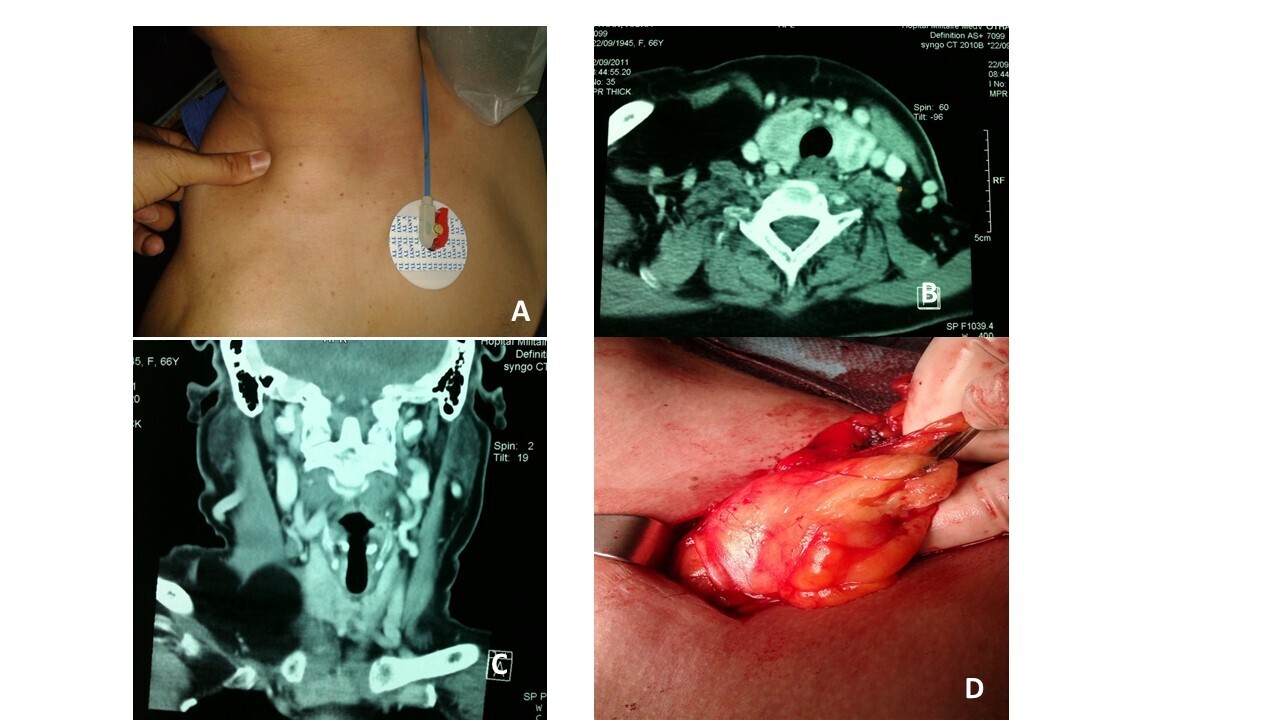

A 66-year-old female patient, completely asymptomatic, presented with a swelling measuring 4 cm (palpable part) in dimension arising from the supraclavicular region and the base of the right side of the neck. On palpation, the mass was smooth, painless, soft in consistency, non-tender, and mobile (Figure 2a). A CT scan of the neck revealed a hypodense mass occupying the lower third of the neck and supraclavicular fossa on the right side with fat density, measuring 15 x 10 cm (a goiter was associated; Figure 2b and 2c). Complete surgical resection of the mass was accomplished through an elective incision in the right supraclavicular fossa (Figure 2d). The postoperative period was uneventful with an acceptable cosmetic result. Pathological studies confirmed the diagnosis of lipoma.